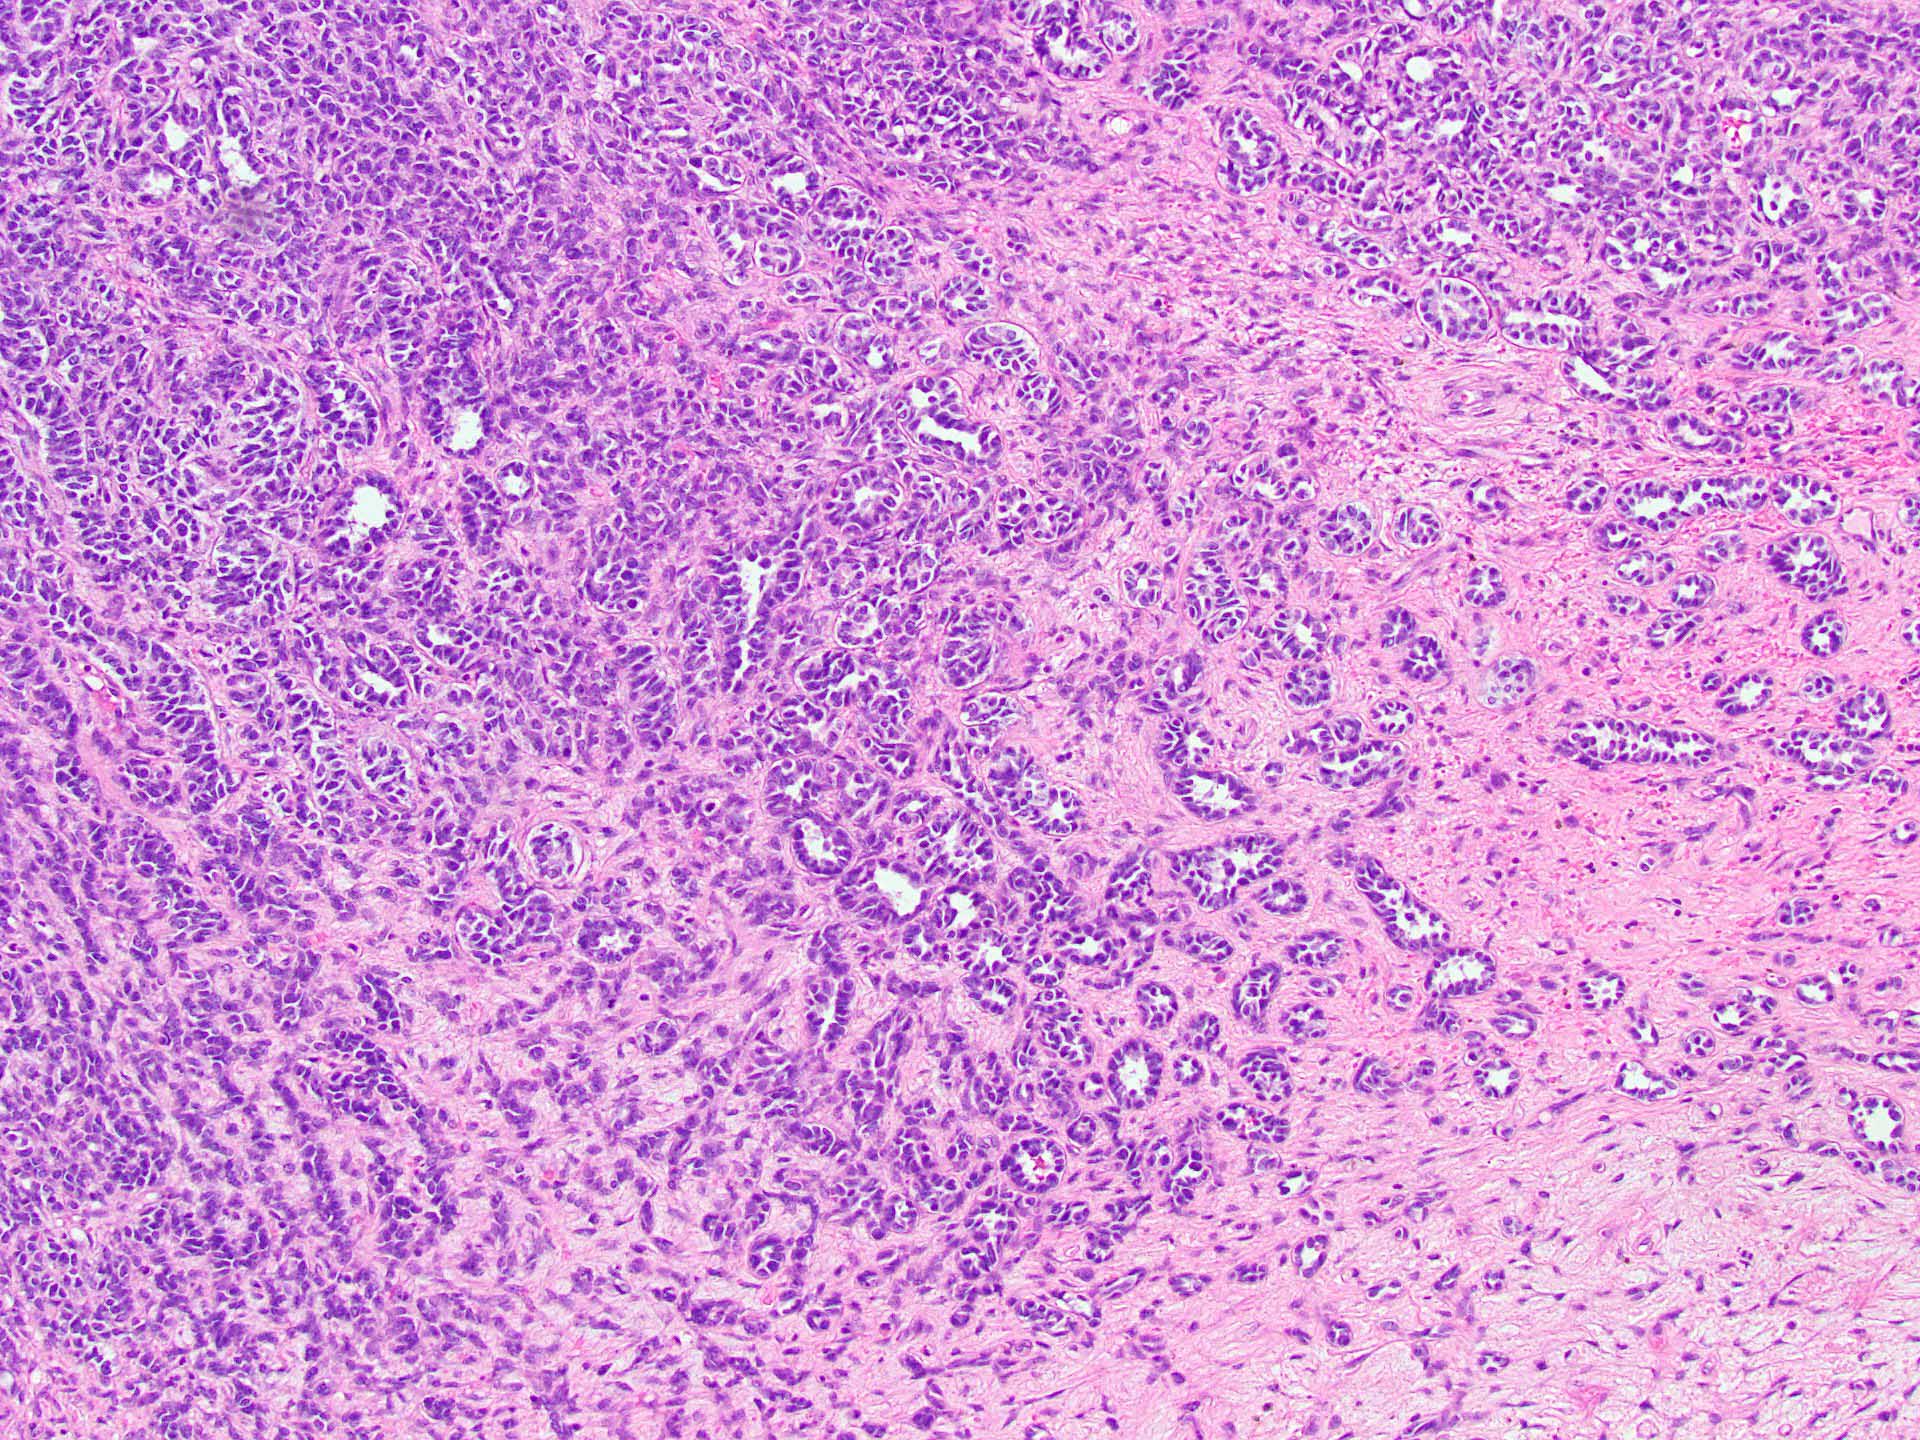

Microscopic (histologic) description

- Tubular pattern (most common and usually present at least focally) with solid or hollow tubules

- Cuboidal or columnar cells

- Bland oval to round, monotonous nuclei

- Pale cytoplasm

- Lipid rich or oxyphilic variants may be associated with Peutz-Jeghers syndrome

- Other patterns: trabecular, diffuse, alveolar, pseudopapillary, reniform, pseudoendometrioid, spindled

- Absent to very rare Leydig cells

- Pathologic features predictive of malignant behavior include 5 mitoses per 10 high power fields, severe cytologic atypia, necrosis and size > 5 cm

- Reference: Am J Surg Pathol 2005;29:143

Microscopic (histologic) images

A 40 year old woman is seen in the clinic with complaints of irregular uterine bleeding and pelvic fullness. Transvaginal ultrasound shows a 9 cm right ovarian mass. The mass is surgically removed and a pathologic examination shows the features in the picture above. The mass is positive for inhibin and SF1. The tumor is negative for EMA, PAX8, MelanA and chromogranin. In which of the following general categories does this tumor belong?

C. Pure sex cord tumor. Sertoli cell tumor is a pure sex cord neoplasm of the ovary composed of Sertoli cells most commonly arranged in a tubular pattern. Sertoli cells are positive for inhibin and SF1. Answer D is incorrect because no Leydig cells, which are positive for MelanA and are stromal in nature, are present. Answer B is incorrect because the tumor is negative for neuroendocrine markers. Answer A is incorrect because the tumor is negative for EMA and PAX8.